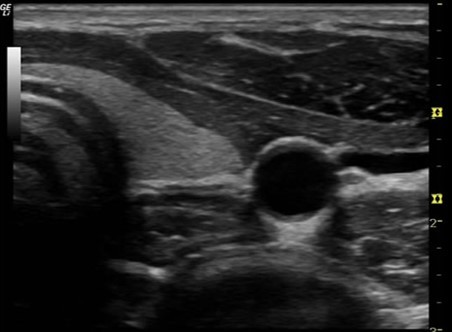

What is B mode?

It is the bright or darker gray dots that display the strength of each echo along a vertical line representing the course of a soundwave.

Describe the x,y,z axis on this picture.